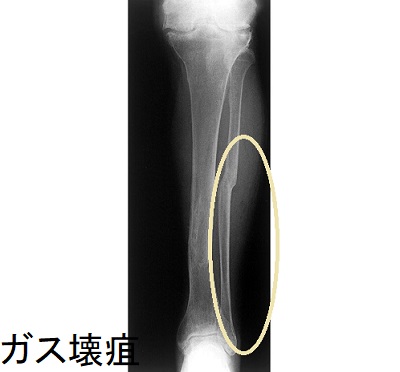

糖尿病ガス壊疽の最も多い原因はClostridium perfringens(ウェルシュ菌)感染。ウェルシュ菌は、嫌気性のグラム陽性桿菌で芽胞を形成し、

- 糖尿病ガス壊疽を引き起こす。抗生剤が効きやすいはずですが血流が悪い足には十分届きません。